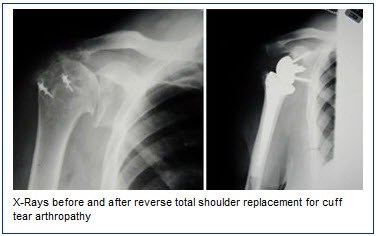

X-raysAnother type of shoulder replacement is called reverse total shoulder replacement. This surgery was developed in Europe in the 1980s. It was approved by the Food and Drug Administration (FDA) for use in the United States in 2004. Reverse total shoulder replacement is used for people who have:

Reverse total shoulder replacement- Completely torn rotator cuffs and

- The effects of severe arthritis (cuff tear arthropathy) or

- Had a previous shoulder replacement that failed

For these individuals, a conventional total shoulder replacement can still leave them with pain. They may also be unable to lift their arm up past a 90-degree angle. Not being unable to lift one’s arm away from the side can be severely debilitating. In reverse total shoulder replacement, the socket and metal ball are switched.

x-raysThat means a metal ball is attached to the shoulder bone and a plastic socket is attached to the upper arm bone. This allows the patient to use the deltoid muscle instead of the torn rotator cuff to lift the arm.